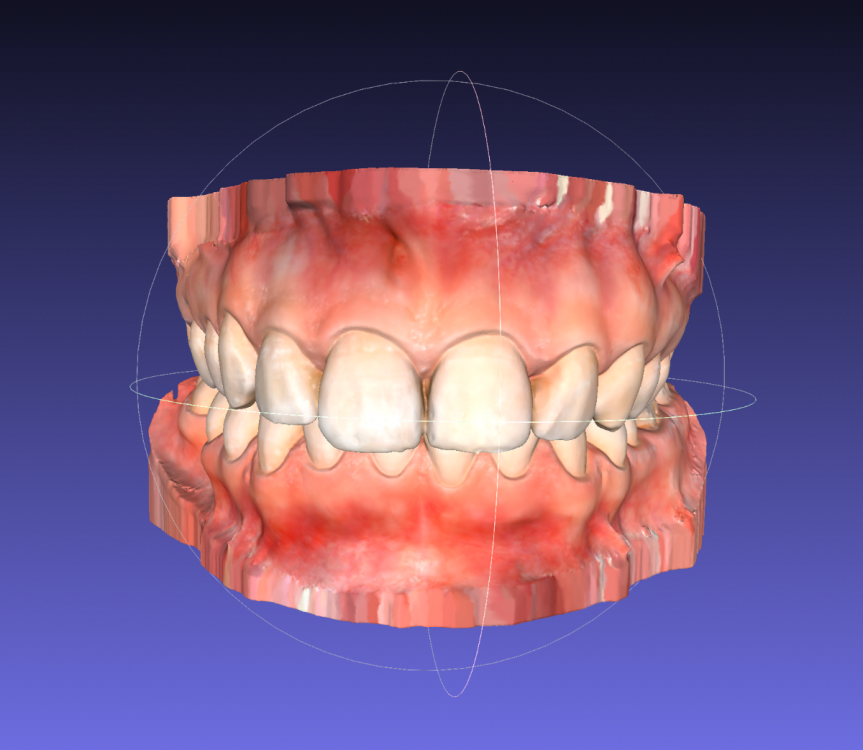

Сейчас я обратилась к ортодонтам с целью выровнять только нижний зубной ряд (искривлен из за воздействия 8ок), с последующей установкой импланта (46 зуб). Нижние восьмерки удалены.

Нужно ли и можно ли двигать верхний ряд?

Лечение планирую исключительно на элайнерах.